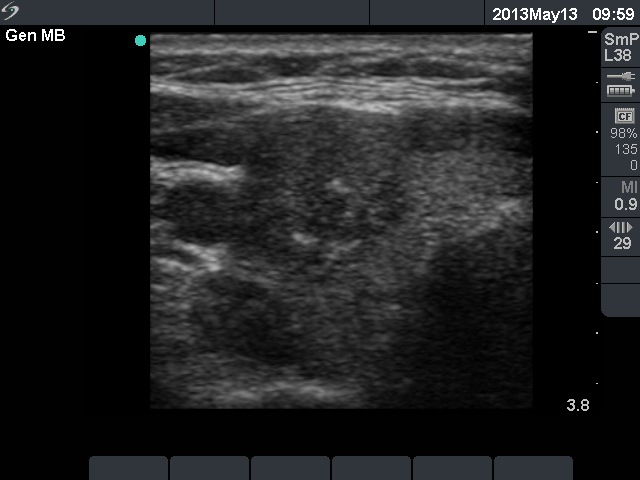

Ultrasonography: there was a hypoechogenic nodule in the right lobe. The nodule displayed hyperechogenic granules and a type 3 vascular pattern.